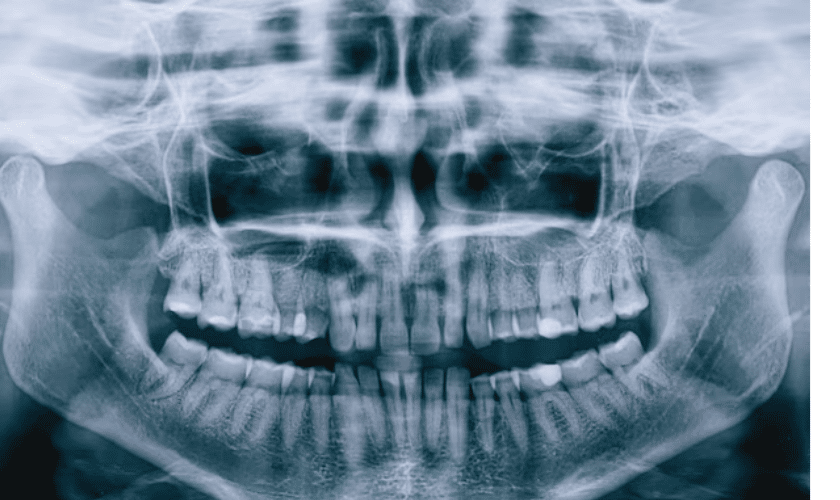

Dental X-ray

X-rays are an important part of diagnosing problems with the teeth and gums. They can help to identify problems such as tooth decay, gum disease, and infections. X-rays are usually taken by a dentist or dental hygienist.

Dental cleanings remove plaque and tartar from your teeth, preventing tooth decay and gum disease. X-rays help your dentist identify problems that cannot be seen with the naked eye, such as cavities between teeth.